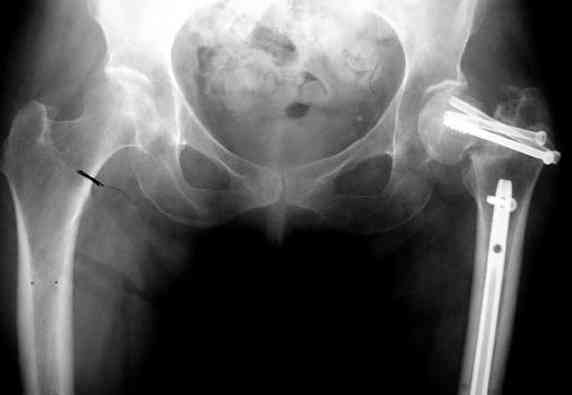

На снимках ложный сустав шейки бедра, несостоятельность фиксации. По положению шурупа можно предсказать ложный сустав, например, если screw backup за кортикальный слой около 15-20 мм, и также изменение угла от первоначального.

№2-3 типичная ошибка несоблюдения концепции параллельности шурупов, нарушение-фиксация поперечным допольнительным шурупом для приближения отломка в результате не сработало метод параллельных шурупов

№4 результат на КТ